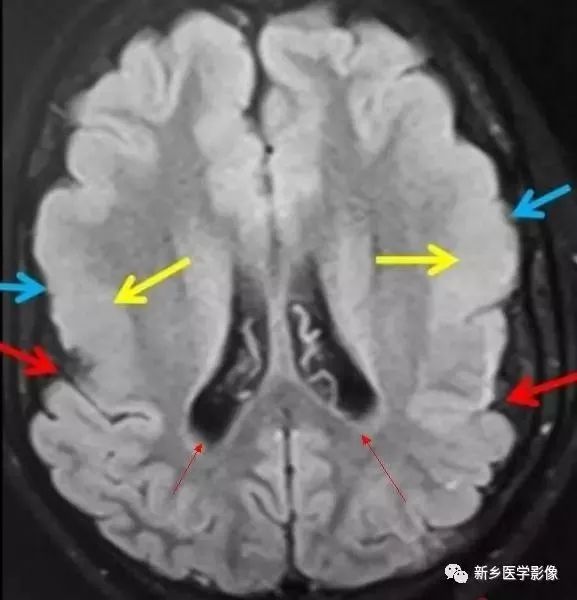

无脑回和巨脑回

无脑回和巨脑回是一组因神经元移行异常所致的脑回发育异常。巨脑回也称平滑脑。巨脑回指有部分脑回存在,这些脑回异常增大增宽、脑沟变浅。巨脑回主要位于额、颞部。无脑回主要位于顶、枕部。

临床上,无脑回和巨脑回畸形患儿均表现有小头畸形和轻微的面部异常,完全无脑回畸形常在两岁前死亡。不完全无脑回畸形通常能长期存活。

CT和MR均能够很好显示无脑回和巨脑回畸形,表现为大脑半球表面几乎呈光滑状,仅可见少数宽阔、粗大、平坦的脑回,脑沟缺如。脑灰质增厚、脑白质变薄,灰白质分界面异常平滑,见不到白质向灰质内伸入的现象。常见透明中隔腔存在,侧脑室扩大,蛛网膜下腔增宽。